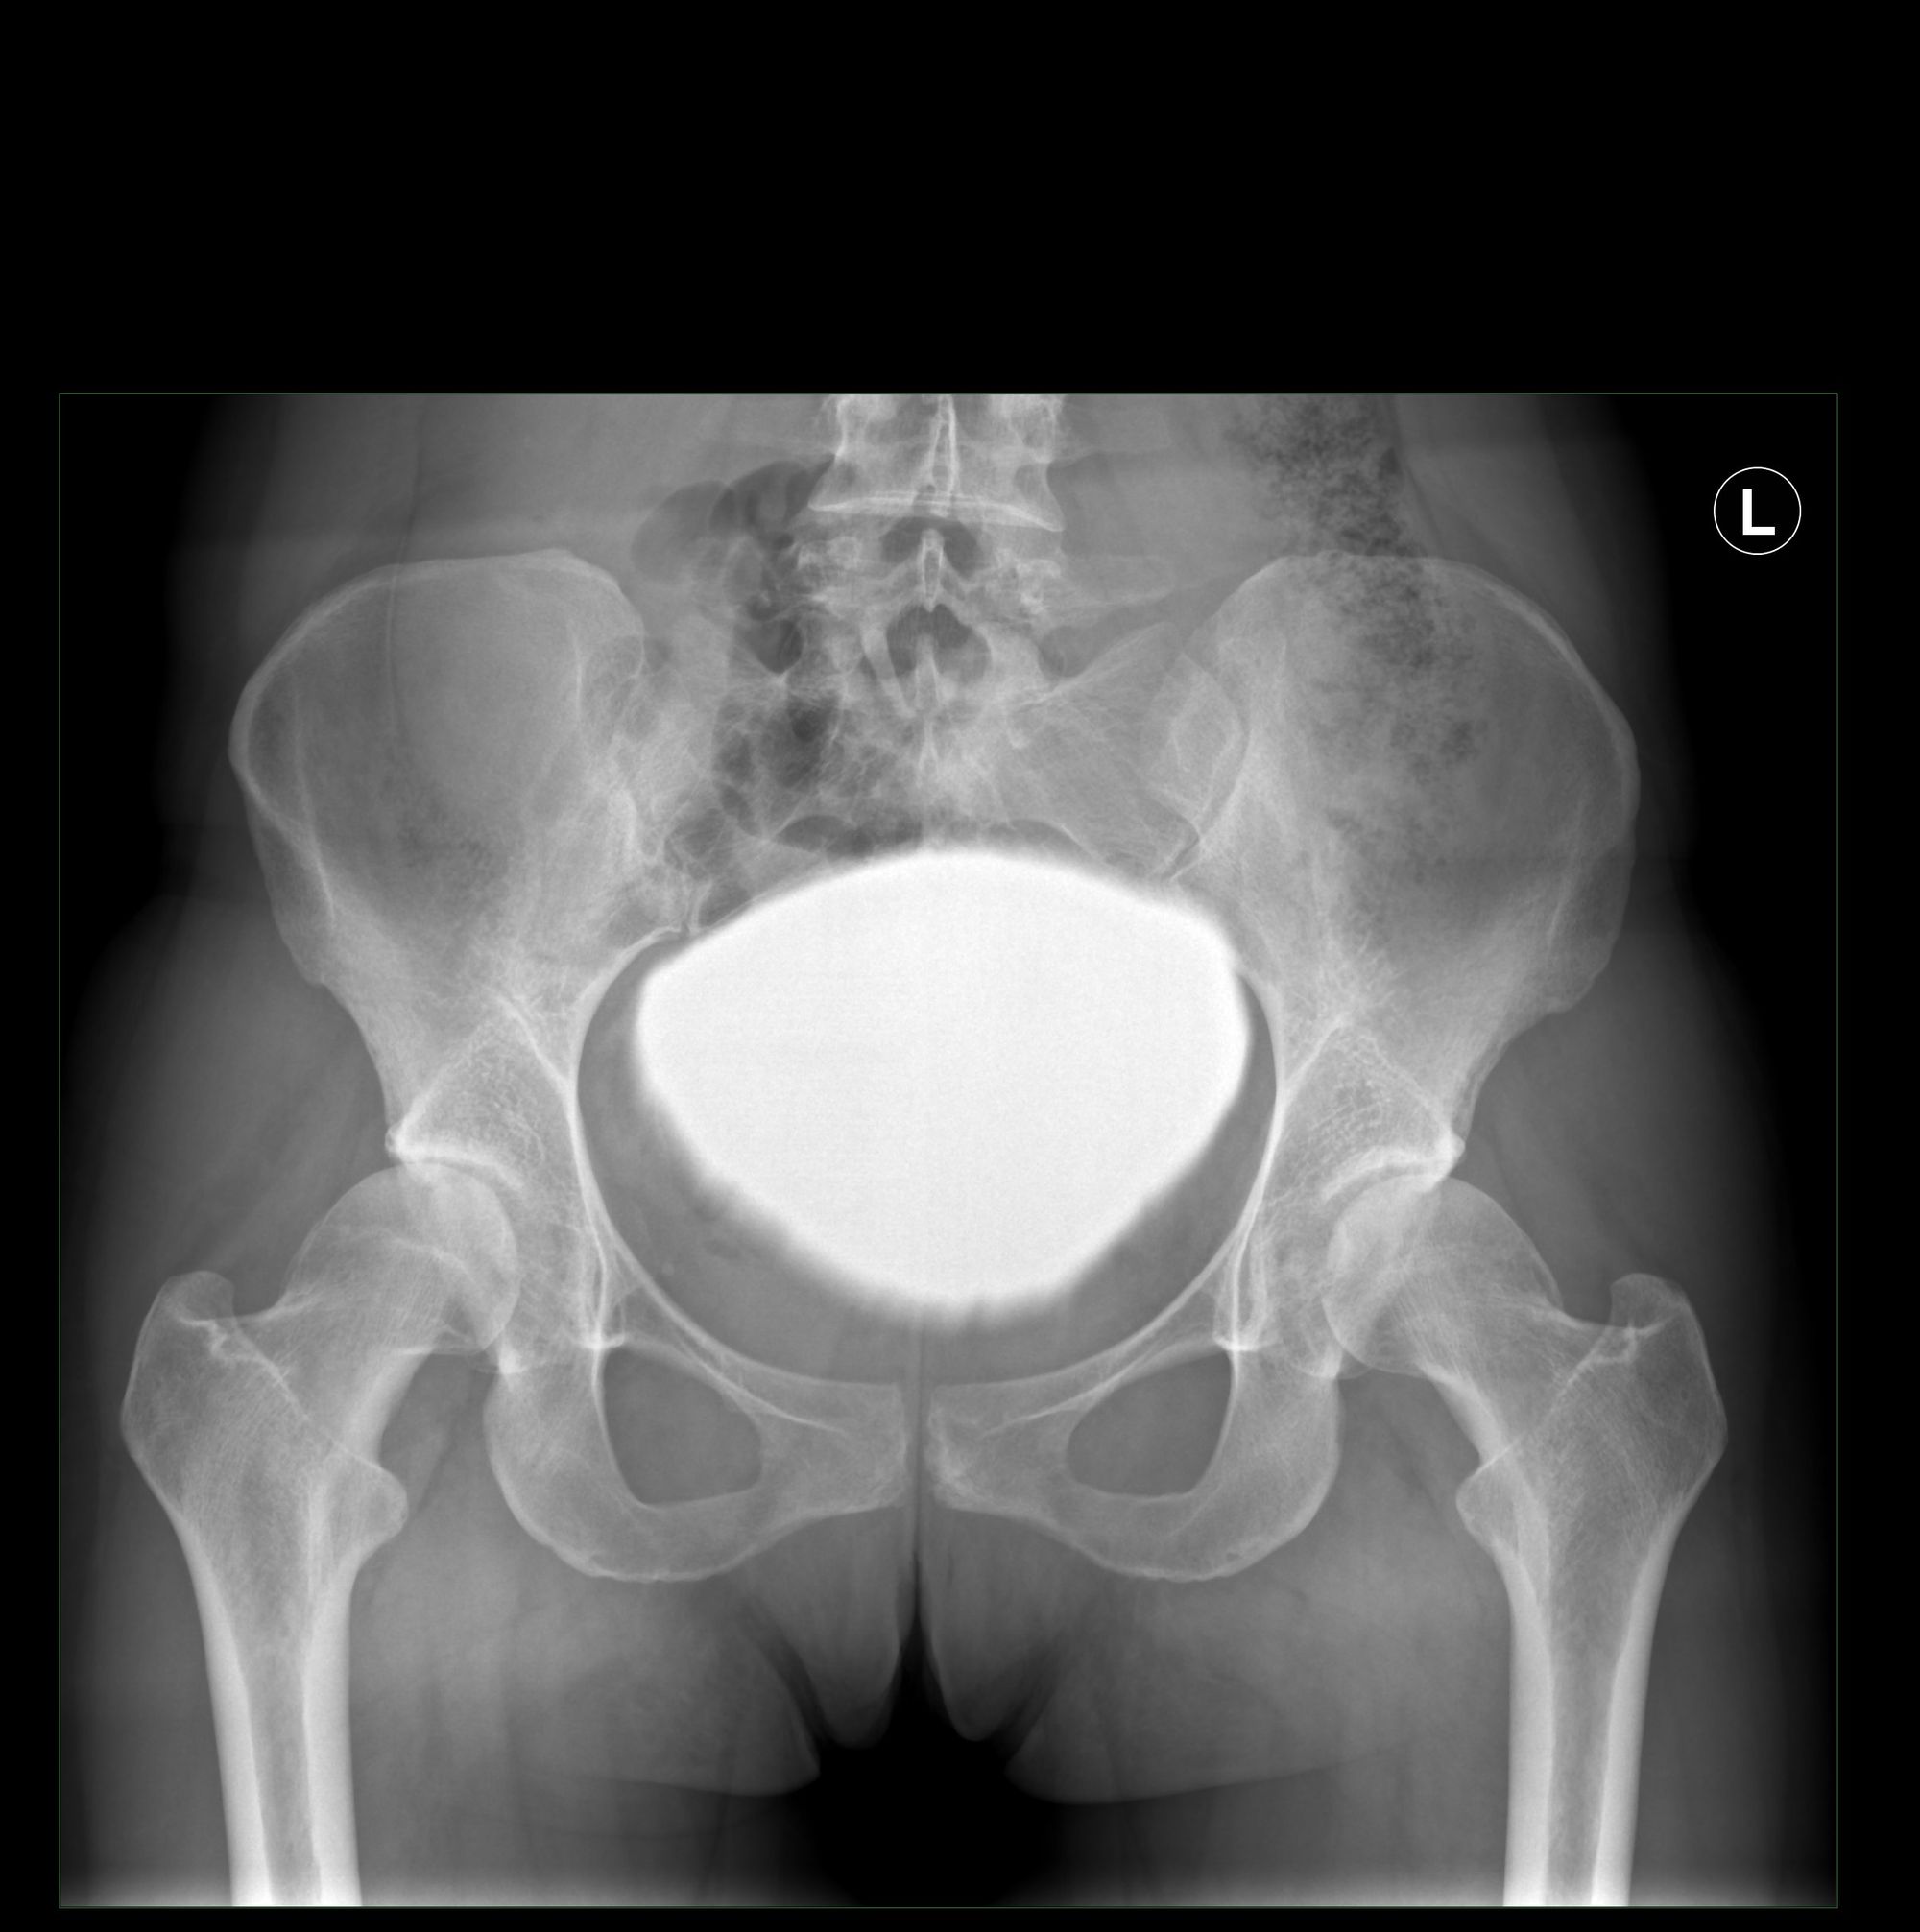

The clinical articles in this issue span a broad range of musculoskeletal conditions. Spinal pathology is addressed through a sublaminar osteotomy technique for lumbar spinal stenosis, while upper extremity care is represented by an update on treatment options for thumb arthritis. Hip preservation is examined via simultaneous periacetabular osteotomy and arthroscopically assisted management of cam-related pathology in acetabular dysplasia. Additional contributions address endoscopic piriformis tenotomy and sciatic nerve release and a modified Tibial Tubercle "Crest" Osteotomy (TCO) for extensile knee exposure.